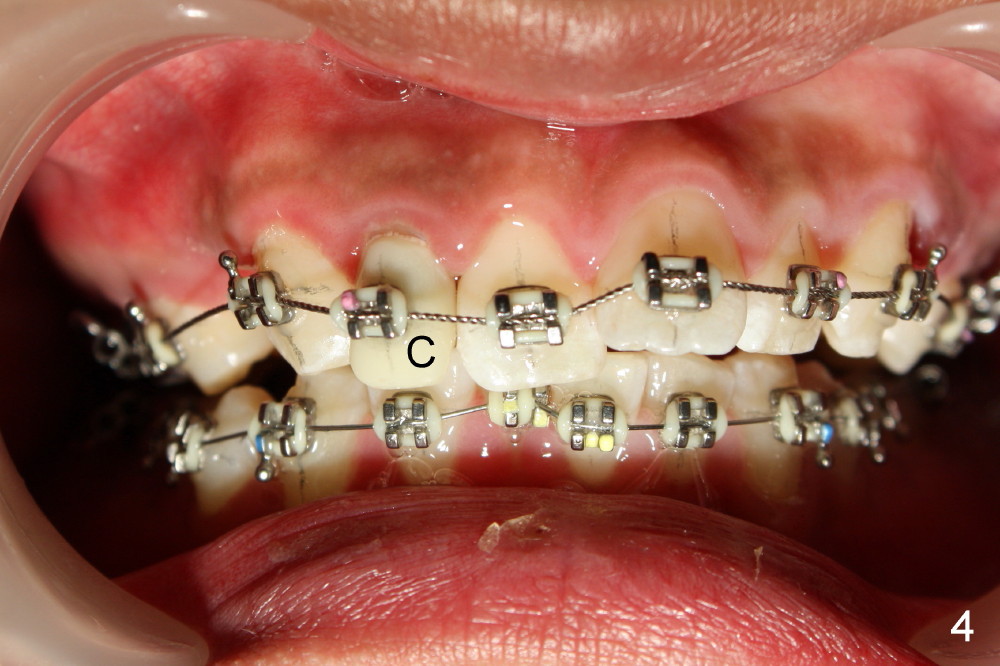

A 21-year-old man has severe maxillary protrusion (Class II malocclusion) with crown fracture of #7 (Fig.1,2,3 (latter two mirror images). Treatment plan is to place pre-fabricated post and provisional for #7 (Fig.4,5 C) and start ortho treatment with extraction of upper 1st bicuspids (Fig.5 *, <). When ortho finishes, fabricate full-coverage porcelain crown for #7.

The 1st step of ortho is arch wire sequence to align the arches (from thin round wires to thick rectangular ones). The 2nd is to retract the canines distal (Fig.1 (planning), Fig.7 (6 months post bracketing), Fig.8 (7 months), using closed coil springs (*). The 3rd step is to move the remaining anteriors together distal using posted wire (^) and again closed coil springs (Fig.9; 8 month into treatment). Note the overjet between upper and lower anteriors (Fig.9: *). This space allows the upper incisors to move backward.